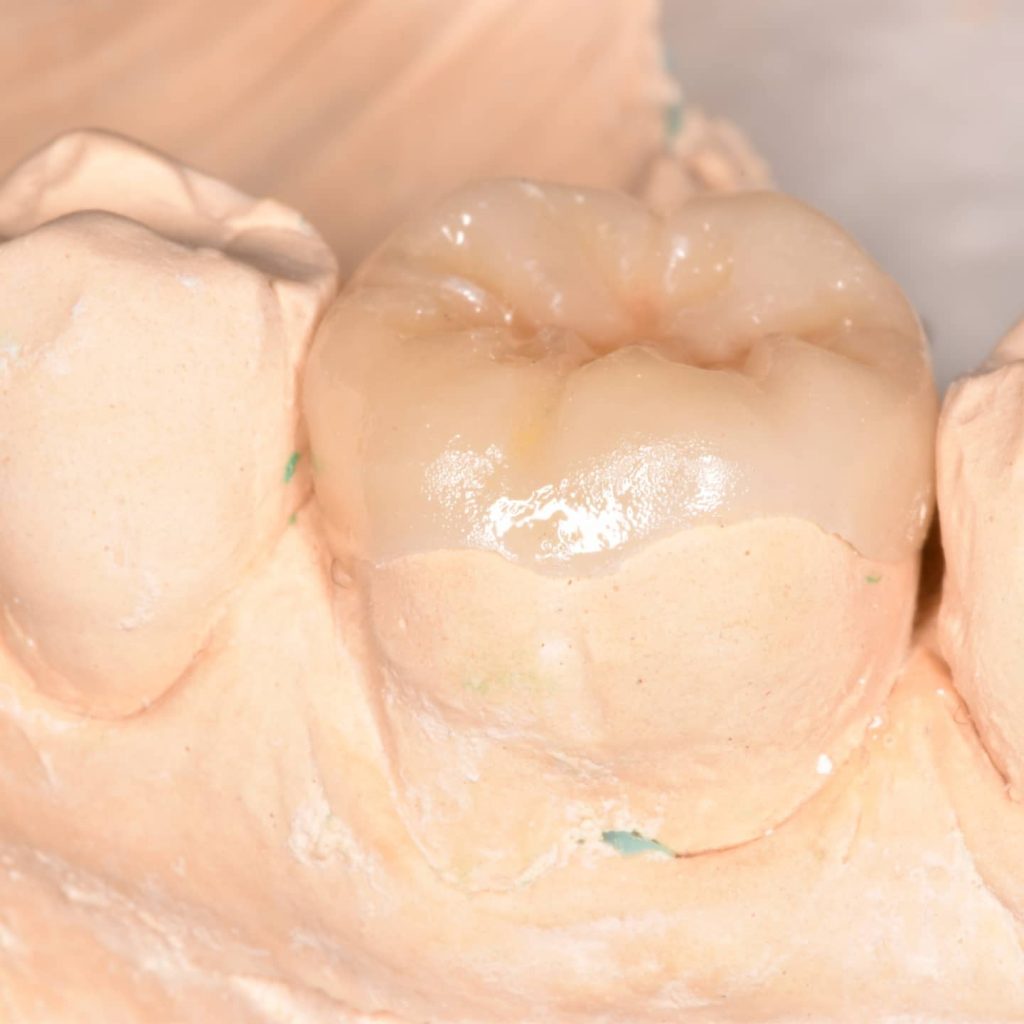

Overlay

After checking the fitness